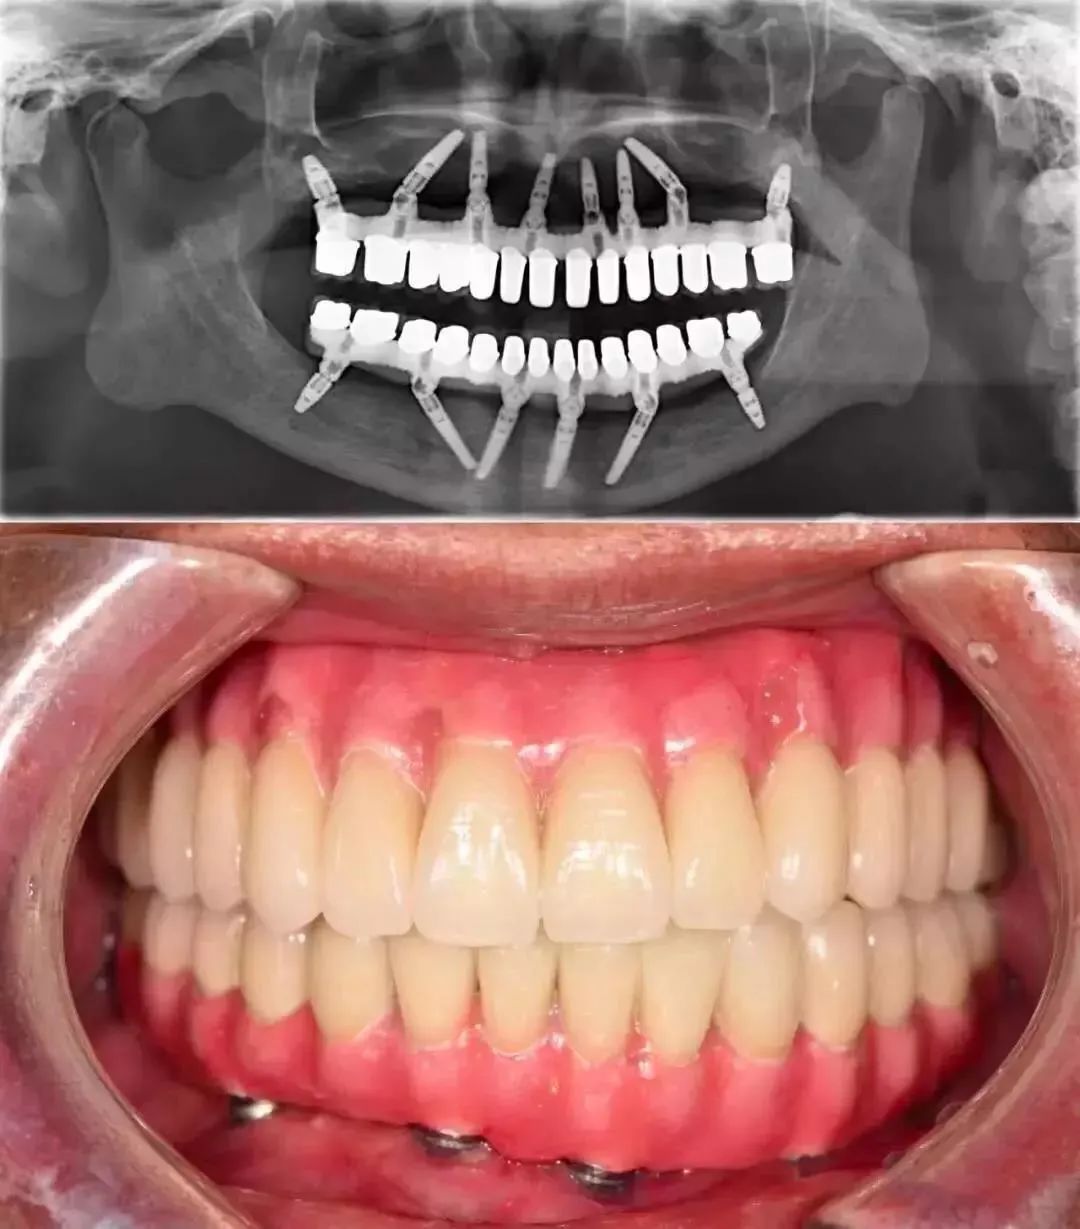

价格高昂种植义齿 图片来源:@种牙匠黄建生